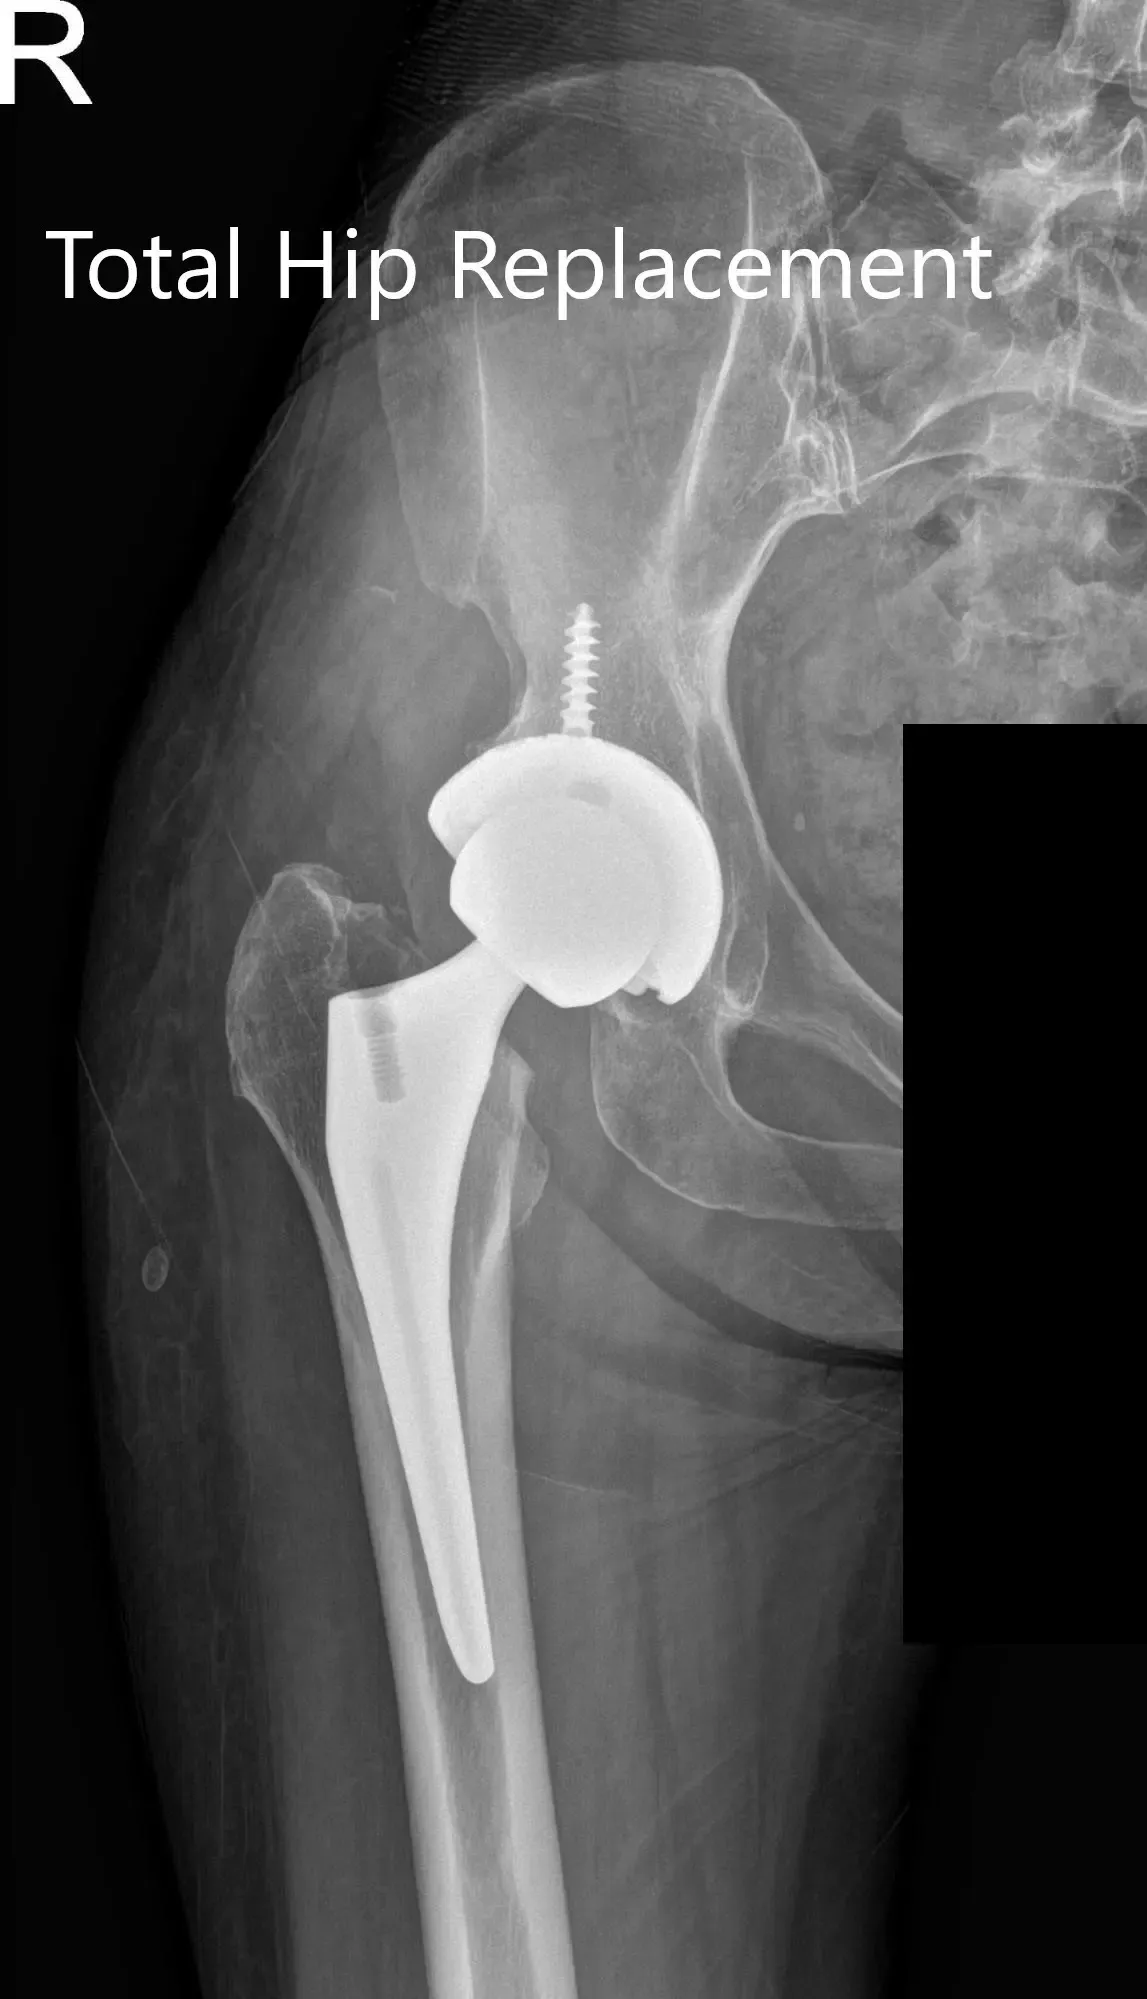

IMPLANTS USED: Ceramic femoral head 36 mm plus with127-degree neck angle system size 2, 30-mm neck length with a stem length 99 mm with a taper 54 mm cup with a 6 .5 mm screw 25 in length.

Postoperative X-ray showing the AP and lateral views of the right hip.